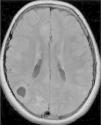

In the 74.3% (26) patients for whom MRIs were available, 76.9% (20) of them had tubers in every cerebral lobe and more than 15 tubers in total, thus presenting high lesion load. Radial migration lines were observed in 96.2% (25) of the patients (Fig. 1). Subependymal nodules were found in 84.6% (22), most of them calcified, and 3 of them enhancing (Fig. 2). Infratentorial tubers were found in 23.1% (6) of the patients. Cyst-like tubers were present in 7 (26.9%) patients, with juxtacortical location in 6, and infratentorial location in 1 (Fig. 3). There was one probable case of giant cell astrocytoma, around the foramen of Monro, measuring less than 1cm, without hydrocephalus (Fig. 4). Focal atrophy was not found in any of the patients.

We reviewed the MR studies of all patients with an identified TCS2 mutation except one, and found a high lesion load in all of them. One of the 5 patients with a TSC1 mutation had a high lesion load. Of the 5 cases associated with refractory epilepsy, 2 had cyst-like tubers.

We found high lesion loads in 87.5% of the patients with cognitive delays and in 78% of patients in whom seizures appeared before 12 months of age. We also found radial migration lines in 89% of the children with early onset of epilepsy.

FLAIR images were used to identify tubers and radial migration lines,18 and T2-weighted FLAIR images to identify subependymal nodules.

Tubers were defined as corticosubcortical lesions with high signal intensity on FLAIR images, and radial migration lines as lines of hyperintensity on FLAIR images extending from the ventricles to tubers in the cortex. Subependymal nodules were found in all ventricles, protruding into the ventricles from the ventricular wall.

Tubers with subcortical cysts were defined as lesions with cerebrospinal fluid signal characteristics on MRI bordered by a hyperintense rim in T2 scans. Tubers and Calcified tubers and subependymal nodules showed low signal in T2 and T2* scans. Since the density of tubers in brain parenchyma is suggested as the best marker of severity of epilepsy and cognitive function1, we performed a qualitative assessment of brain tubers density by estimating the frequency of tubers in each cerebral lobe. The density of tubers reflects brain lesion load, obtained by evaluation of the total number of tubers and involvement of each brain lobe by tubers. High brain lesion load was considered if all cerebral lobes contained tubers in patients with total number of more than 15. Quantitative assessment with automatic segmentation of tuber density or brain volume occupied by tubers was not performed due to inaccessibility to appropriate software.